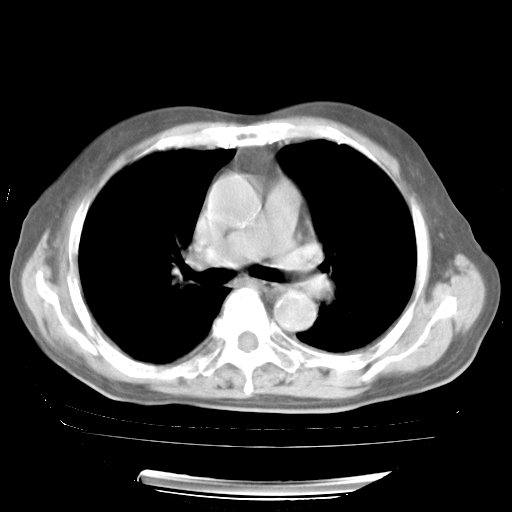

轻微咳嗽,无痰,(体温正常时)R20次/分,P75次/分,双肺底、腋下可闻及少量捻发音。下肢轻度浮肿。

ECG:右心室增大

心脏超声检查:无右心室增大。